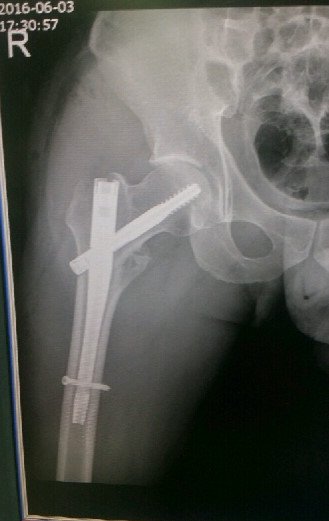

철심을 이렇게 박았습니다.

저는 실려가서 허벅지 뼈가 부러지는 대퇴골 골절상을 비롯해 가슴 팔 다리 부분이

찢어지는 상해를 입었습니다. 다시 큰 대학병원으로 옮겨서 대퇴골 골절 수술을 했습니다.

철심 길게 하나 양쪽으로 2개 핀1개꽂고 대수술을 했습니다. 수술걸린시간은 5시간정도고요

이수술은 거의 노인분들만 하고 젊은층은 10%도 안되는 수술이라고하네요....

목발은 3개월정도 짚어야되고 허벅지에 철심은 1년뒤에 다시 빼는 수술을 해야한다고 ....